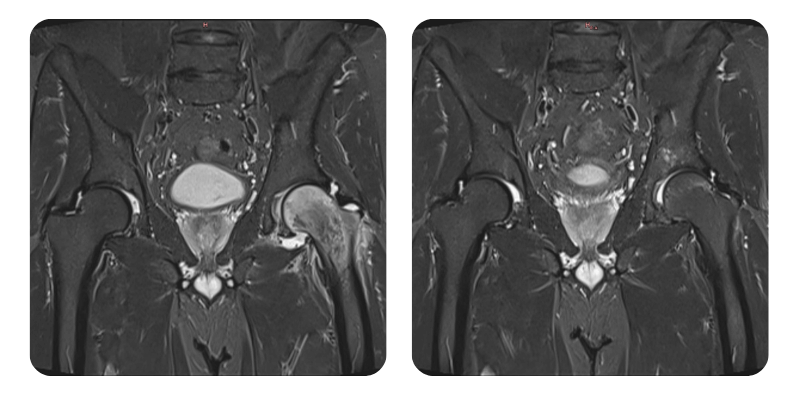

Prima

Dopo

J.A.V., 43 anni - Edema della testa femorale sinistra

Si osserva una riduzione dell'edema superiore al 90%, in correlazione con il quadro clinico, e il paziente e considerato guarito.